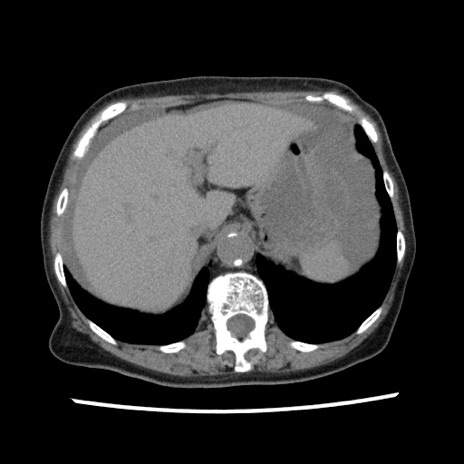

【症例】80歳代女性

【主訴】腹痛

【現病歴】8時間前から腹痛あり来院。

【既往歴】糖尿病、脂質異常症、子宮体癌にて子宮全摘術

【身体所見】意識清明・会話良好だが腹痛で苦悶様、全腹部にわたって反跳痛と圧痛あり

【データ】WBC 13600、CRP 0.14、LDH 224、CK 90